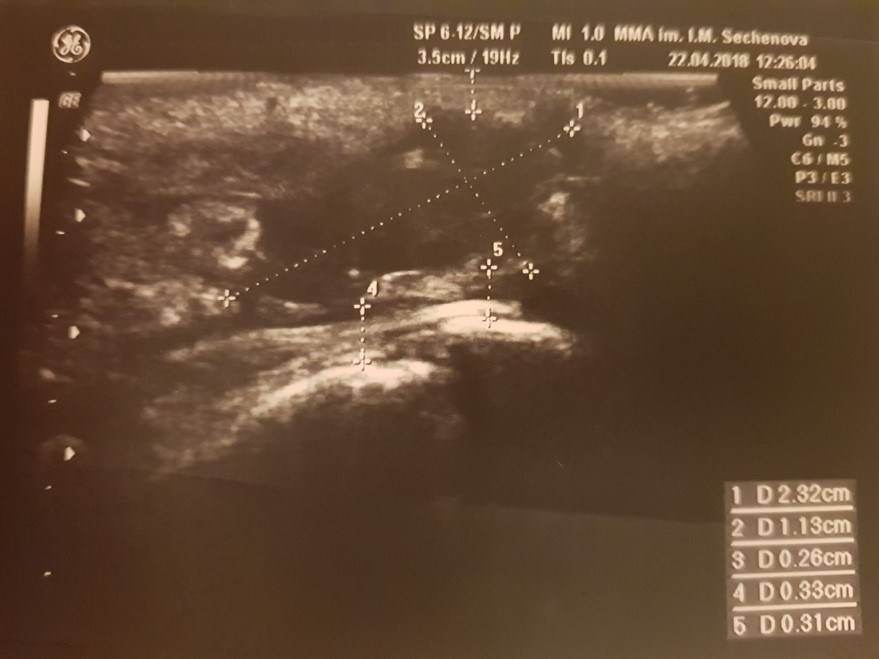

1. УЗИ мягких тканей крестцово-копчиковой области. Этот метод диагностики позволяет оценить размеры, распространенность процесса, наличие связи между гнойными полостями, выявить глубоко расположенные абсцессы, определение которых при помощи осмотра и ощупывания этой области невозможно. УЗИ позволяет хирургу заранее определится с объемом оперативного вмешательства, спланировать методику закрытия кожного дефекта после удаления ЭКХ (рис.5).

Рисунок 5. УЗ-картина эпителиального копчикового хода в проекции межъягодичной складки

(при УЗ-исследовании мягких тканей, непосредственно под кожей, в толще подкожно-жировой клетчатки

определяется неоднородное образование размерами 25х32 мм с ровными четкими контурами с

включениями)